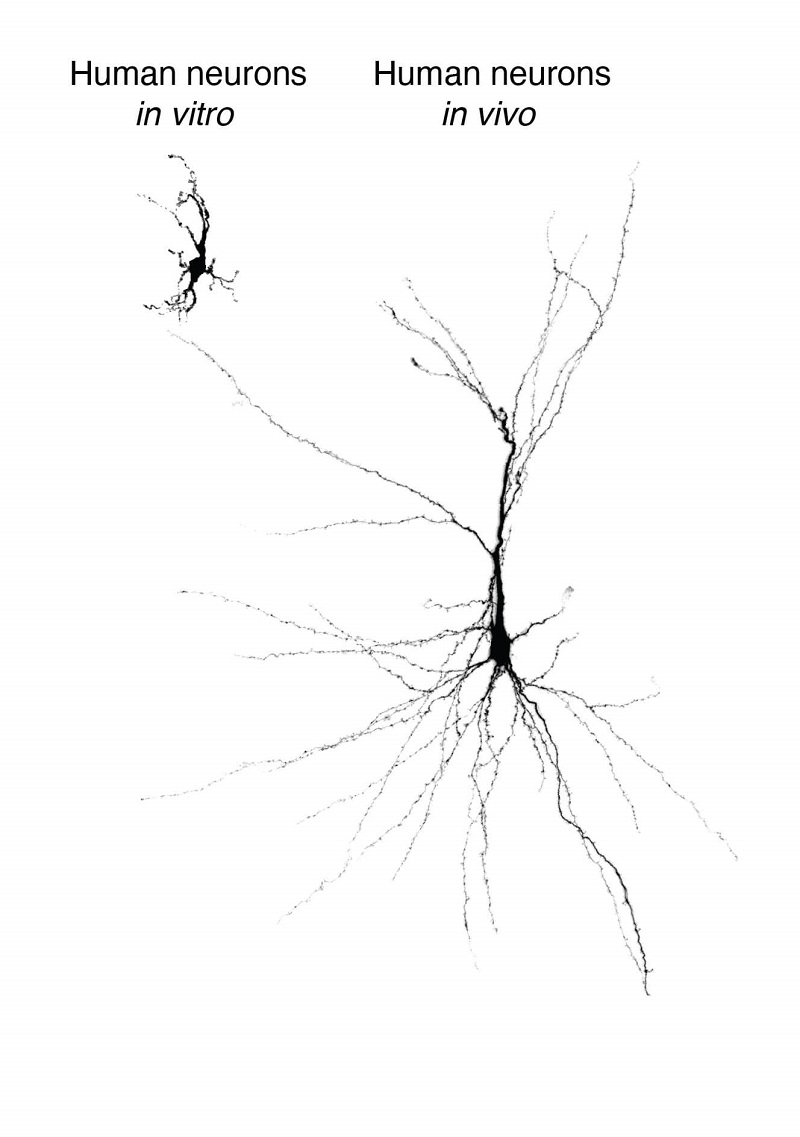

人干細胞培養的大腦類器官是一種很有潛力的平臺,可以模擬人類發育和疾病。然而,體外生長的類器官缺少在真實有機體中存在的各種連接,這會限制類器官的成熟,讓它們無法與其他控制行為的神經環路整合,因而會影響類器官模擬具有遺傳復雜性和行為特征的神經精神疾病的能力。之前的研究試圖將人腦類器官植入成年大鼠的大腦,但這些細胞在植入后無法完全成熟。

來自干細胞的重建人類神經元,在培養皿中維系并移植到大鼠大腦皮層中。

圖片來源:斯坦福大學

美國斯坦福大學研究團隊此次將人腦類器官植入新生大鼠大腦的體感皮層中,體感皮層是負責從全身接收和處理感覺信息的腦區,包括觸覺。他們發現,該類器官能發育成熟,部分能與神經環路整合,并在大鼠大腦中具有功能性。這種整合讓研究人員能在人細胞的活動與動物習得行為之間建立關聯,證明植入的神經元可以調節大鼠的神經元活動,并能誘導追求獎賞的行為。